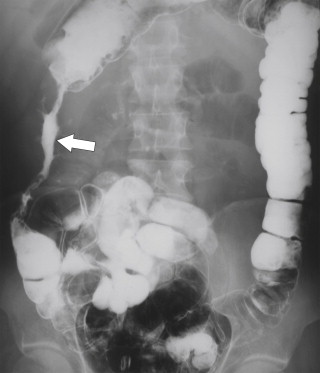

Plain radiography may demonstrate an ileus, sometimes confined to the left colon. As the disease progresses, bowel wall thickening develops ( Fig. 5-34 ) with a toxic megacolon if severe ( Fig. 5-35 ). BE is now rarely performed, but results demonstrate thickened folds and ulceration, either linear or with mucosal sloughing. Healing can lead to stricture formation ( Fig. 5-36 ). The findings are now usually made by CT and are similar to other forms of colitis (inflammatory bowel disease, infectious colitides, and radiation colitis if the radiation field included the colon). The disease is suggested in the appropriate clinical setting and by the left-sided distribution of the colonic changes ( Fig. 5-37 ). Severely affected patients show colonic pneumatosis as the gas permeates the damaged mucosa, which can then enter the mesenteric venous system and be recognized as mesenteric venous gas (particularly at CT) and ultimately intrahepatic portal venous gas. Occasionally, ischemia occurs proximal to an obstructing colonic stricture, such as colonic adenocarcinoma. The obstruction causes marked distention of the proximal colon, compromising its vascular supply or directly invading mesenteric vasculature ( Fig. 5-38 ).

Figure 5-36, BE in a 71-year-old man with a left mid-descending colon stricture ( arrow ) secondary to fibrosis from prior ischemic colitis.

Figure 5-37, Axial ( A and B ) and coronal ( C ) contrast-enhanced CT in a 66-year-old woman with diffuse left colonic mucosal thickening ( arrows ) due to ischemic colitis. Note the normal right colon ( arrowhead ).